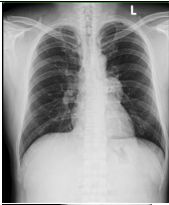

2. A 27-year-old woman had productive cough for one month.